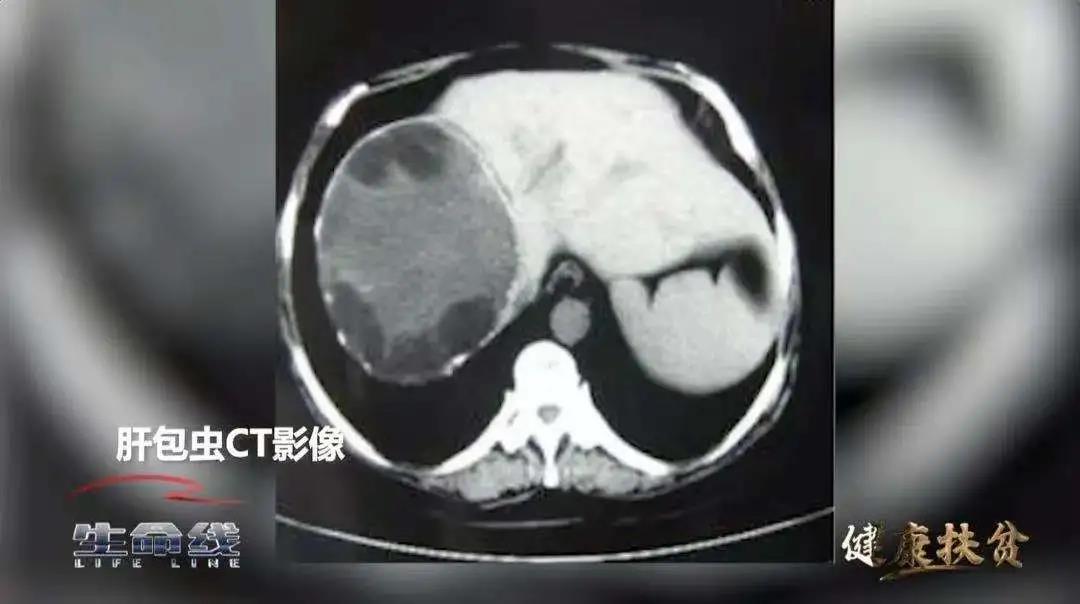

包虫病,是一种主要流行于我国西部农牧区的人畜共患的寄生虫病。其潜伏期长,早期不易发现,特别是泡型包虫病,可以向周围组织侵蚀,甚至向更远的器官转移。根据世界卫生组织的相关资料,未经治疗的泡型包虫病患者10年病死率高达94%,因其致死率高,又被称为“虫癌”。全国受包虫病威胁人口曾一度达到5000余万。